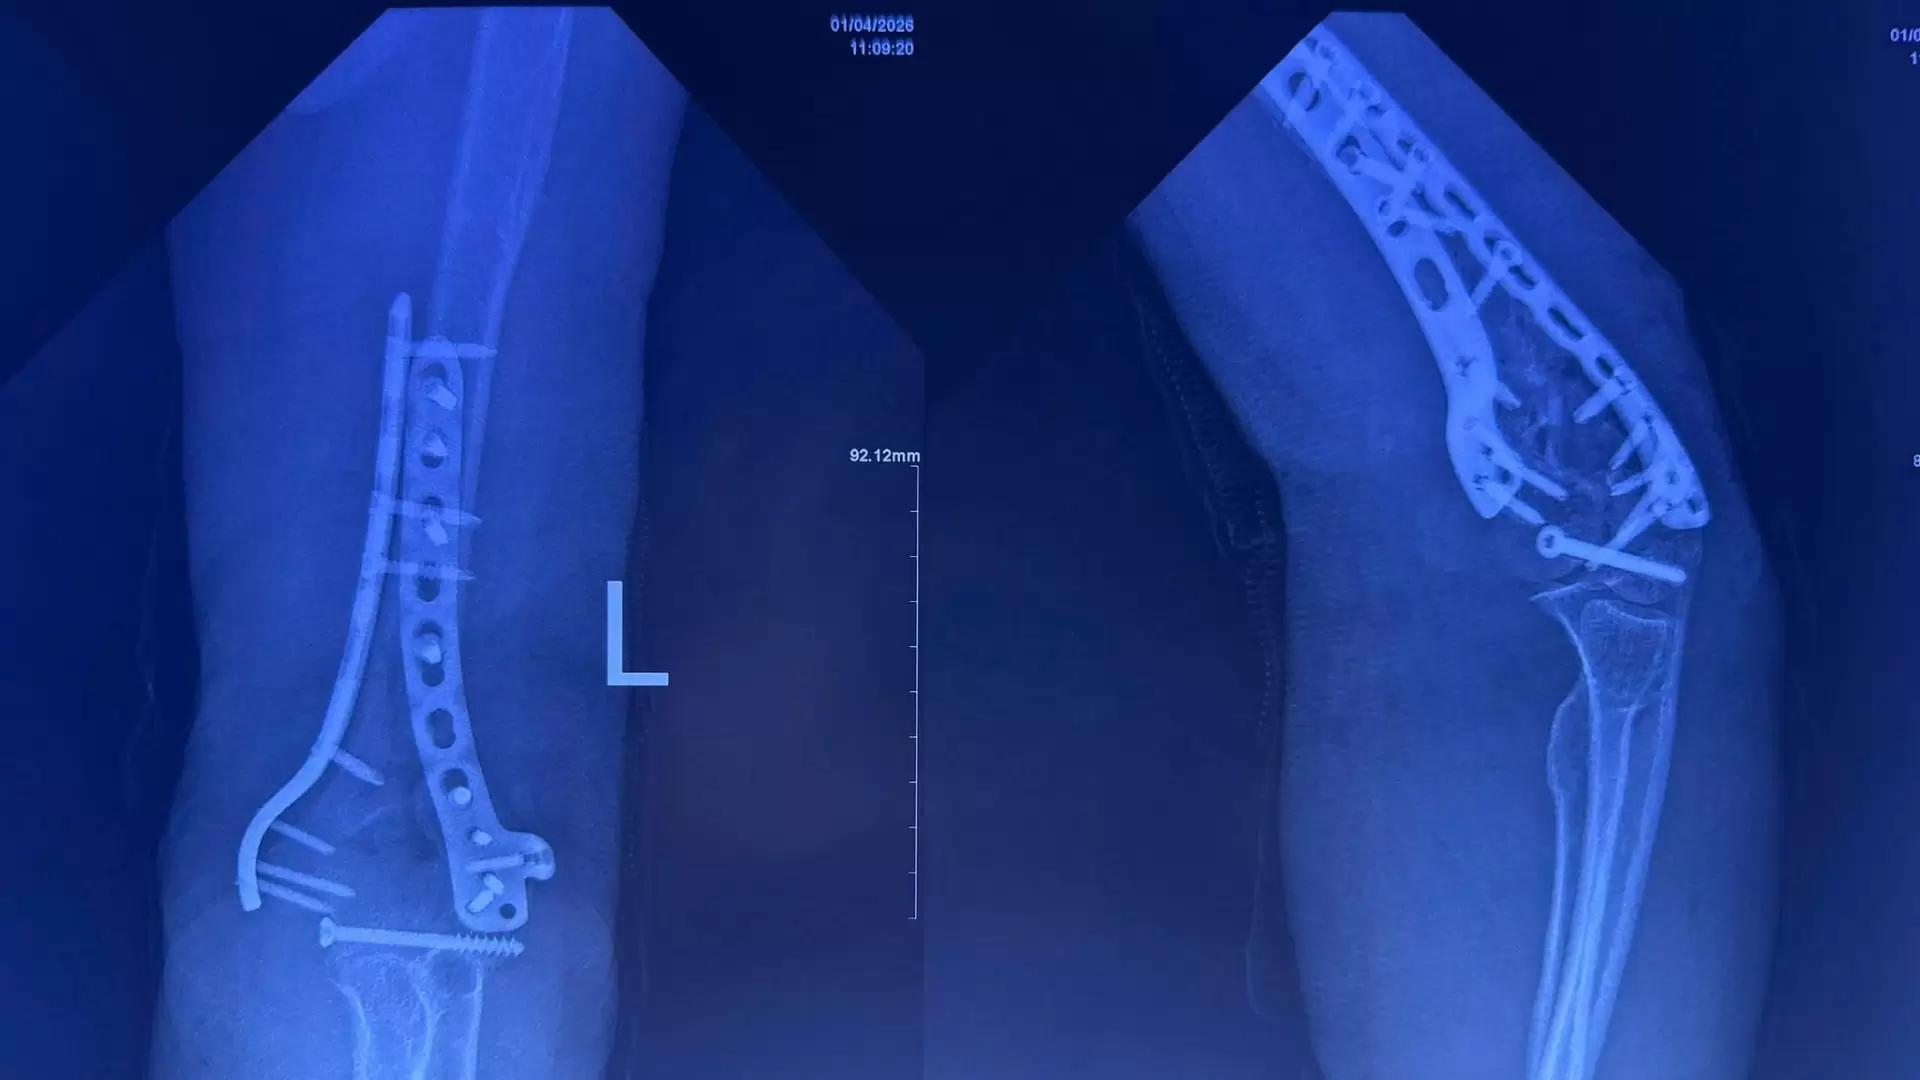

1. Trường hợp 1: Bệnh nhân bị “Tam chứng đau khổ” (Terrible Triad) ở khuỷu tay: gãy mỏm vẹt, chỏm quay kèm trật khớp. Đội ngũ bác sĩ đã thực hiện kết hợp xương nẹp vít, kim Kirschner và khâu đính dây chằng để tái tạo sự vững chắc cho khớp.

2. Trường hợp 2: Gãy hở phức tạp vùng khuỷu và cẳng tay. Các bác sĩ đã áp dụng chiến lược “Phẫu thuật hai thì”:

– Thì 1: Cắt lọc, cố định tạm thời để ngăn ngừa nhiễm trùng.

– Thì 2: Điều trị thực thụ, kết hợp xương bằng nẹp vít và kim Kirschner để phục hồi giải phẫu, cố định khớp

Kết quả vượt mong đợi

Chỉ sau 2 tuần phẫu thuật, cả hai bệnh nhân đều có vết mổ liền tốt và đã phục hồi được phần lớn biên độ vận động khớp khuỷu. Đây là minh chứng cho sự chuẩn bị kỹ lưỡng, rút ngắn thời gian mổ và chăm sóc hậu phẫu tích cực tại bệnh viện. Đây là minh chứng cho hiệu quả của hướng tiếp cận đa mô thức tại bệnh viện An Bình, giúp giảm thiểu nguy cơ tàn phế cho người cao tuổi.